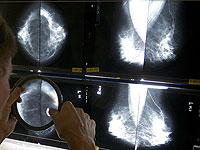

ИИ лидирует по точности прогнозирования риска рака груди

Модель ИИ, использующая изображения маммографии для оценки пятилетнего риска развития рака молочной железы, продемонстрировала более точное и надежное распределение женщин по группам риска по сравнению с традиционной оценкой плотности молочной железы. К таким выводам пришли исследователи в новом исследовании, которое представят на ежегодной конференции Радиологического общества Северной Америки (RSNA).